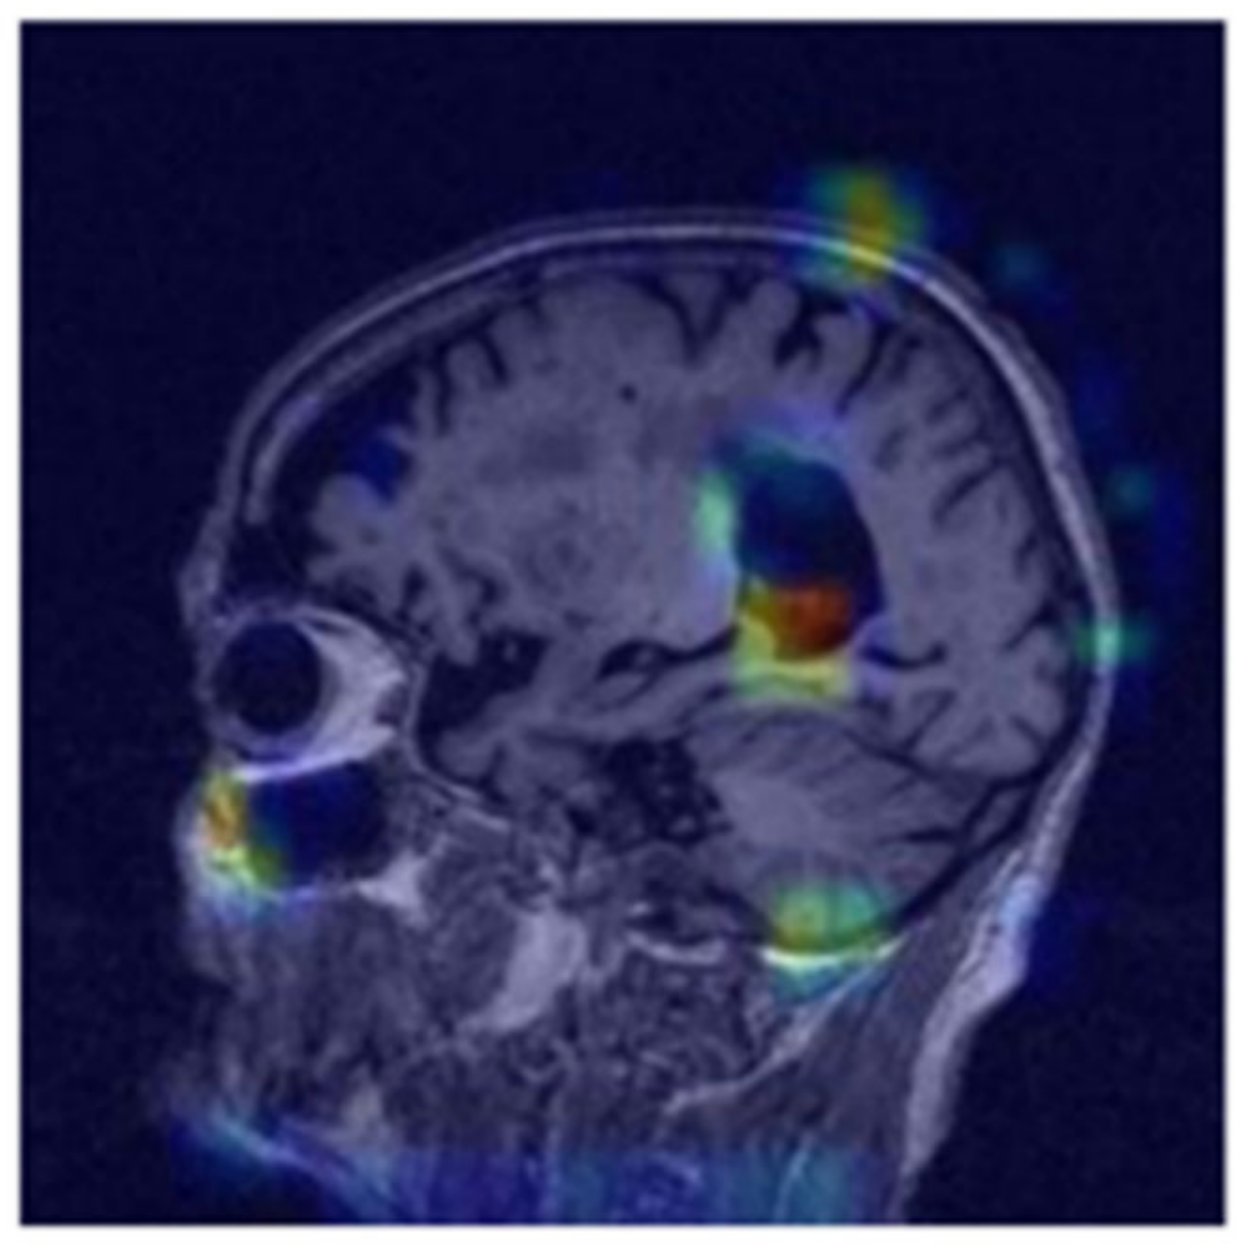

where ReLU, the rectified linear unit activation function, sets negative values to zero, k   is the sum of all activation maps, w k ( c ) represents the weights relative to the k -th activation map for class c , and A k is the k -th activation map. The ultimate standardized heat map accentuates the areas upon which our deep learning algorithm relies to provide predictions [8,9,25,26,27]. We employed a channel-wise self-attention mechanism to highlight significant features within each channel of the input tensor (Figure 8). This mechanism was accomplished through two convolutional layers with (1, 1) kernels that generate an attention map, which is then element-wise multiplied with the input tensor. The initial convolution layer, followed by a ReLU activation, formed an intermediate representation, while the subsequent convolution layer with a sigmoid activation created the attention weights. These weights adjust the emphasis on different channels, enabling the model to enhance or reduce specific features, thereby improving the learning process and overall performance [24,28,29,30].

The challenges associated with diagnosing and predicting the progression of Alzheimer’s disease (AD) have been mitigated by using artificial intelligence (AI), particularly in image data analysis. However, in contrast to various brain disorders, AD remains difficult to comprehend despite being relatively easier to categorize based on established features. This study utilized the glass-box methodology to illustrate that the deep learning model generated positive predictions corresponding to the specified characteristics. What makes this research unique is the employment of the channel-wise attention mechanism not only to the deep learning model but also the XAI model, as shown in Figure 9, wherein the left shows the base Grad-CAM with a generalized heat map while the right shows the model with channel-wise attention applied, returning a well-defined heat map. The image on the left of Figure 9 was created using traditional Grad-CAM and, in comparison to our approach that hinges on an attention mechanism, it is evident that the heat map generated with channel-wise attention highlights the region of interest more accurately, which is in line with the medical literature on MCI diagnosis. The hippocampal area shows early signs of degradation for cases of mild cognitive impairment. While conducting this study, a few challenges were met during the conceptualization process. It was not straightforward when deciding which techniques to experiment with in order to avoid redundant output while supplementing the study collectively. Since the quickshift method is highly sensitive, it called for gradual hyperparameter tuning to obtain an acceptable kernel size of 70. The application of this mechanism improves the quality of the explanation on a more granular scale in contrast to traditional tuning, since each channel in the feature map is considered separately, wherein the focus is only on the most relevant channels. This approach verifies the classification while enhancing localization and the overall scope of this methodology is not limited to MRI studies; our method can be employed for generalized imaging tasks such as object detection. The flexibility of this framework also allows for experimentation with multimodal data such as MRI and diffusion tensor imaging (DTI).

The LIME Explainable Artificial Intelligence (XAI) model developed superpixels that highlighted the cortical atrophy of the gyri and the expansion of the sulci and ventricles resulting from cellular degeneration in its positive prediction for MCI. The Grad-CAM Explainable Artificial Intelligence (XAI) model generated a heat map that revealed the highest activity concentration in regions near the parahippocampal gyrus, corresponding to the distinctive pathological features of Alzheimer’s disease (AD). In the early stages of AD, this region has a significant neuronal loss, characterized as mild cognitive impairment. These explainable artificial intelligence (XAI) solutions can effectively bridge the trust gap and enable medical practitioners from other fields to confidently make accurate assessments, utilizing AI as a transparent and supportive tool.

Figure 8. Jet heatmap of positive values using self-attention for class-specific interpretability with gradient-weighted class activation mapping. The highest level of intensity in the heatmap is observed in close proximity to the hippocampus.